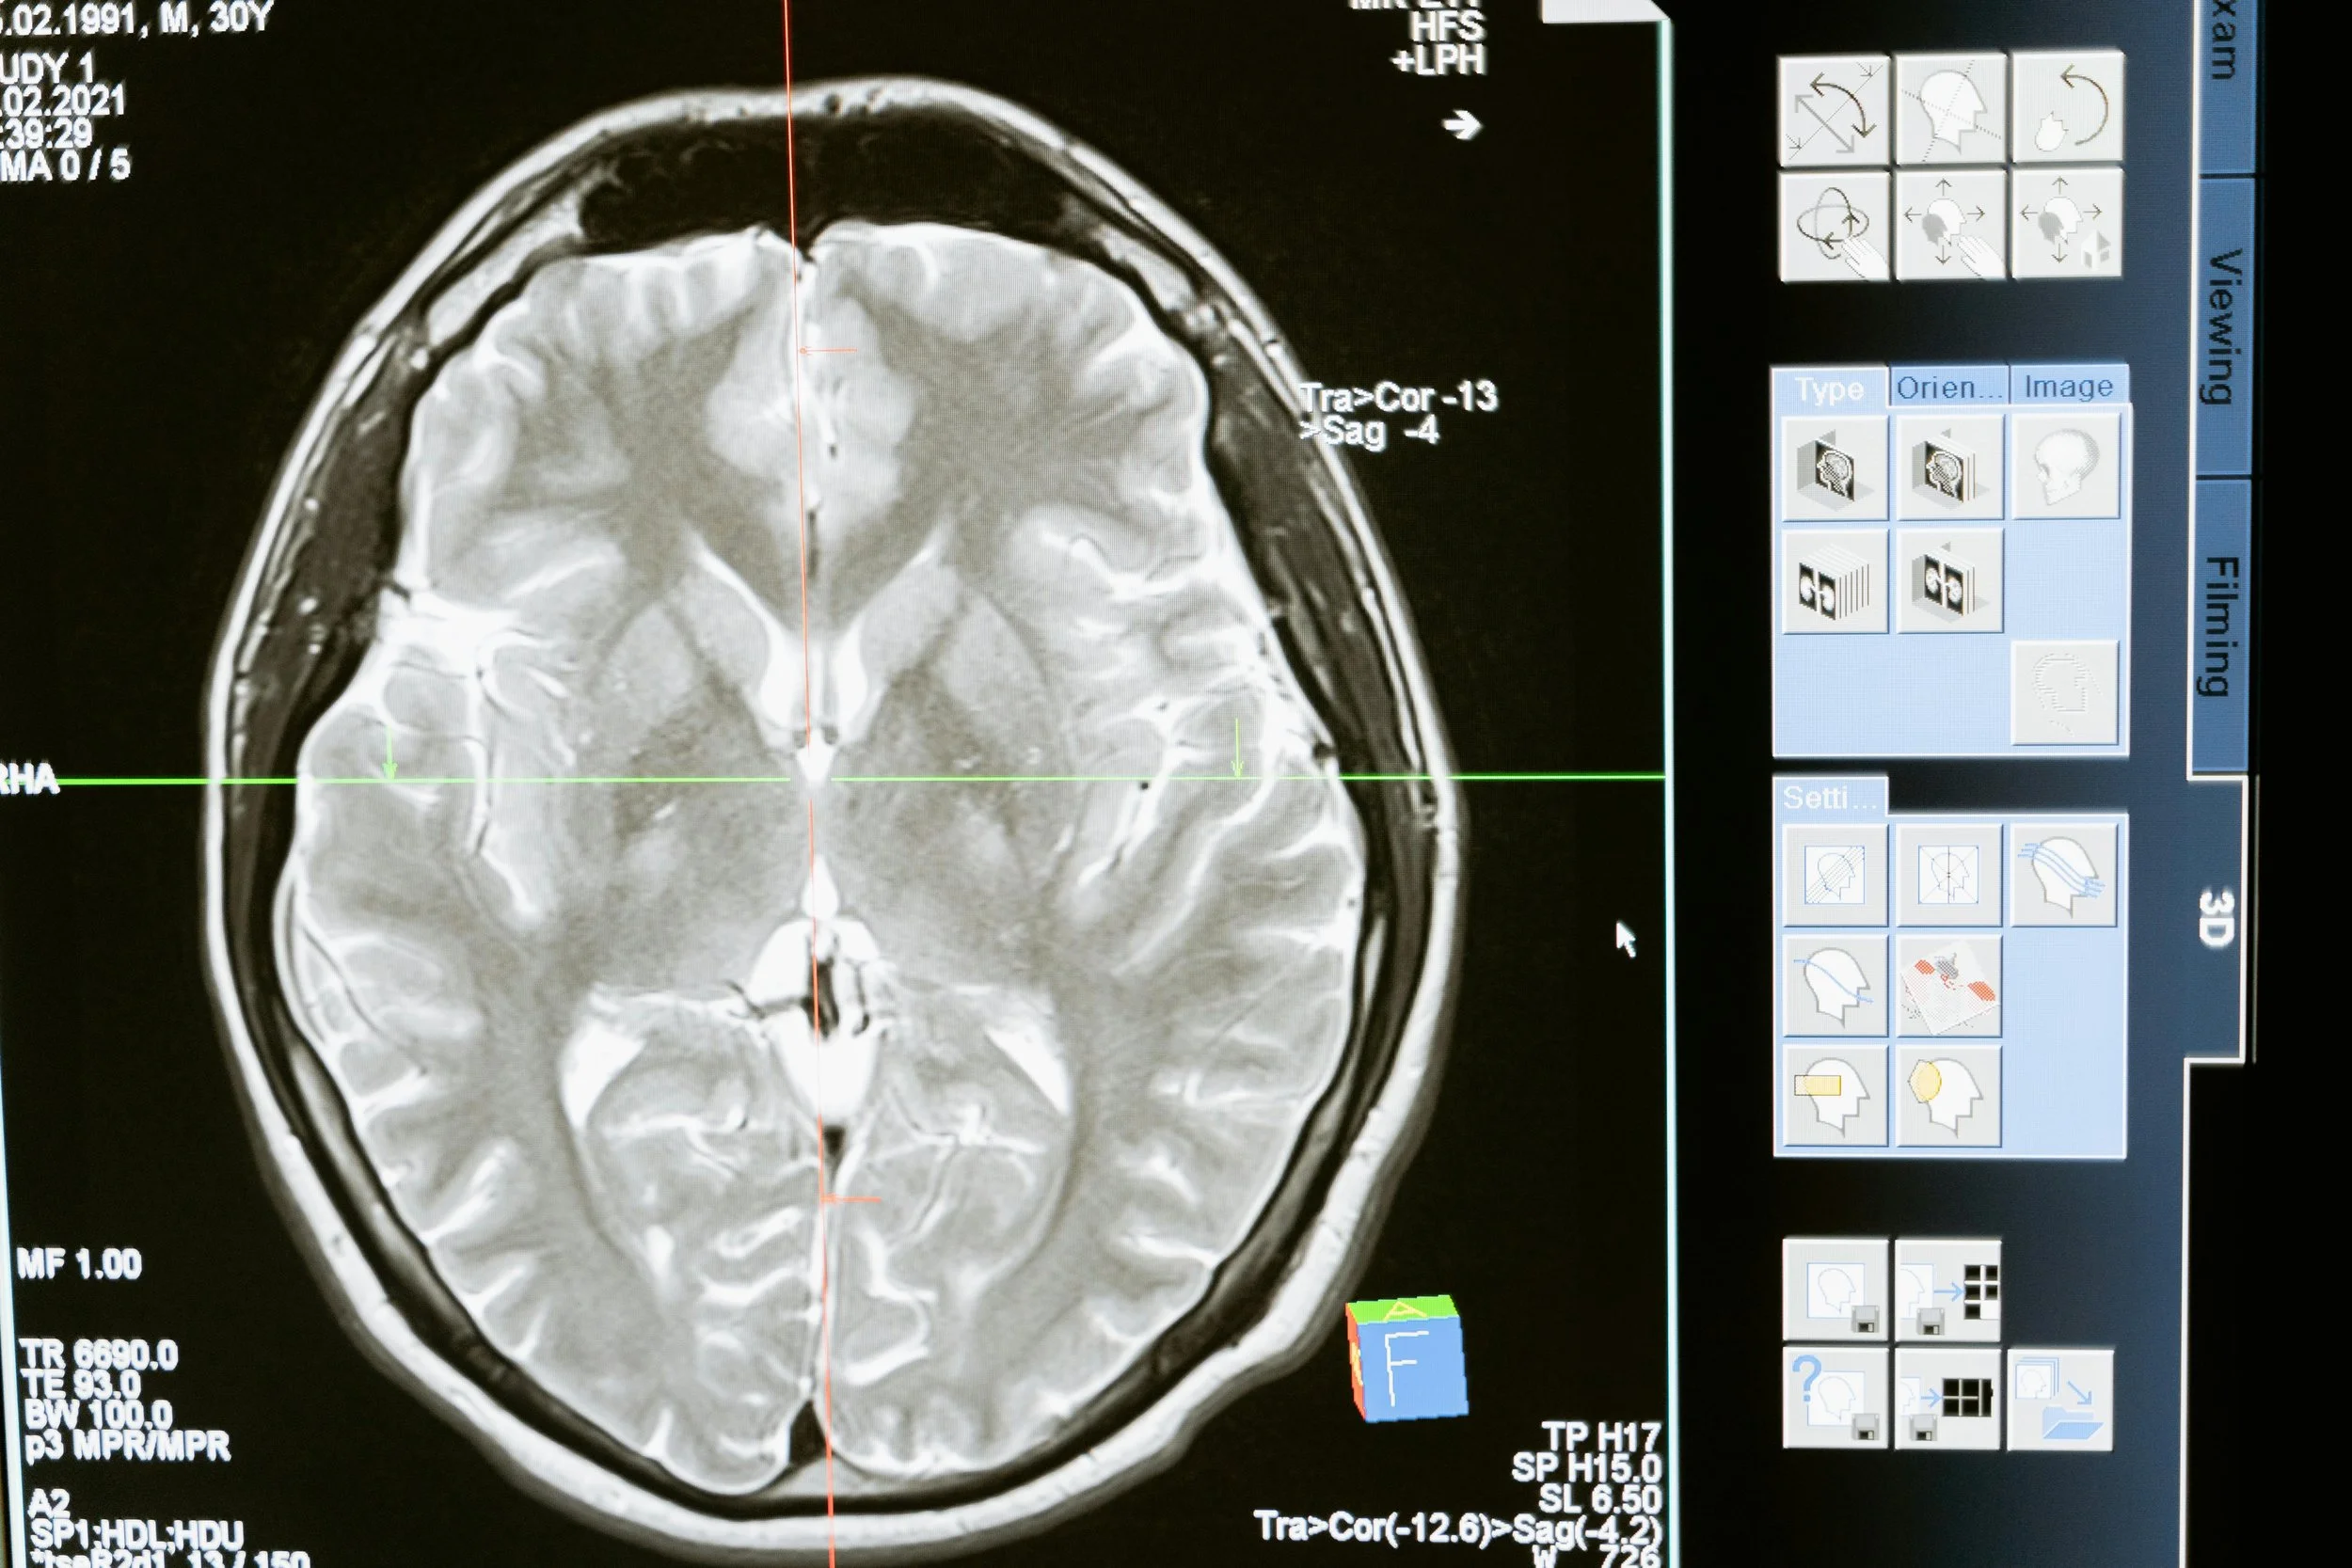

What Happens in Brain Injury Rehabilitation — and Why It Matters for Long-Term Wellness

From acute care to community reintegration, brain injury rehab helps restore daily function and quality of life. Explore how tailored treatment drives better outcomes.